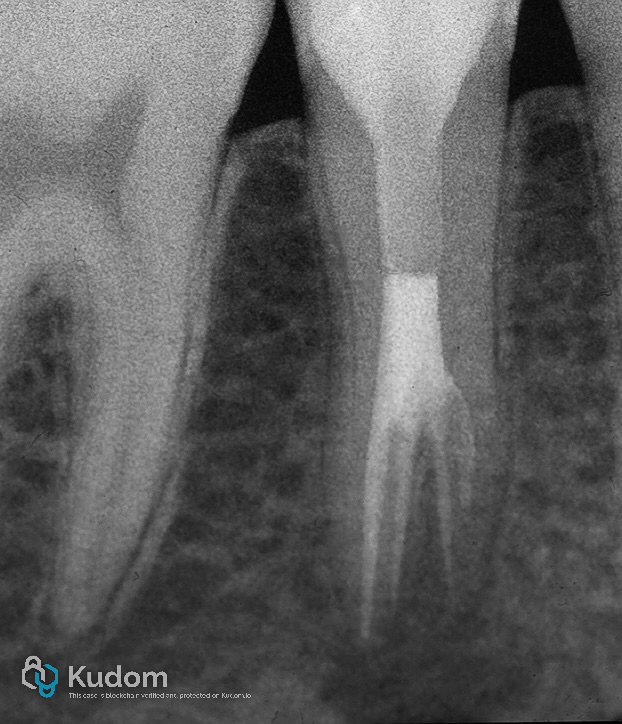

Patient Presentation:

A 19-year-old male patient presented with a severely compromised tooth 45, characterized by an extensive carious lesion leading to the complete loss of the clinical crown. Despite the advanced structural damage, the tooth was asymptomatic upon clinical and radiographic examination.

Root canal therapy was initiated under rubber dam isolation. Anatomical exploration revealed a complex canal system with three distinct canals, including one with a C-shaped morphology. Thorough cleaning, shaping, and obturation were performed using standard endodontic protocols tailored to the intricate anatomy.